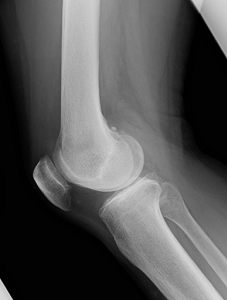

変形性膝関節症、関節リウマチ、外傷による後遺症などで、リハビリテーションや注射などの保存的な治療の効果が得られない状態までダメージを受けてしまった膝関節は、症状が回復する可能性が低く、日常生活が制限されるほどの非常に強い痛みを伴います。特に軟骨が完全に欠損してしまった場合は細胞治療などを行っても軟骨は完全には再生しないため効果は乏しいです。